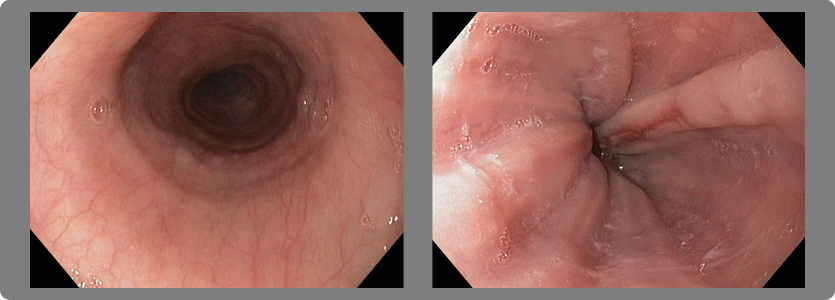

2- Estrechez (estenosis) del esófago

Cuando la esofagitis es grado C o D se producen múltiples cicatrizaciones de la pared y eso origina retracción de la misma con la consiguiente estrechez del esófago y dificultad para tragar (disfagia).

3- Esófago de Barrett

Es una condición en la cual la mucosa del esófago distal, que normalmente está cubierta de epitelio escamoso, cambia a epitelio columnar como consecuencia del RGE y puede evolucionar hasta un cáncer muy maligno.